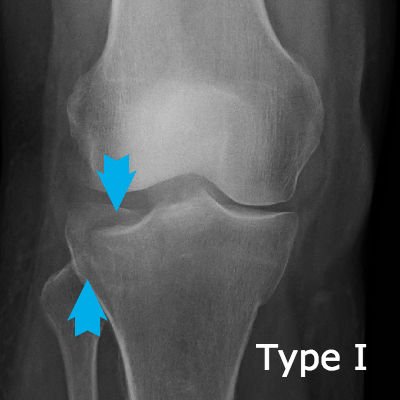

Tibial plateau fractures are very significant because the break goes through the joint line and upsets the dynamics of the joint. This X-ray shows a Schatzker Type I fracture.

Tibial plateau fractures are graded according to the Schatzker classification, so that anyone reviewing the patient's notes have an idea immediately of the severity of the problem.